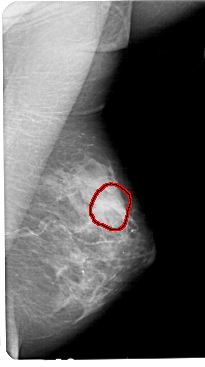

A_1447_1.RIGHT_MLO

LEFT_MLO LINES 5491 PIXELS_PER_LINE 3091 BITS_PER_PIXEL 12 RESOLUTION 43.5 NON_OVERLAY

FILE: A_1447_1.RIGHT_MLO.OVERLAY

TOTAL_ABNORMALITIES 1

ABNORMALITY 1

LESION_TYPE MASS SHAPE LOBULATED MARGINS OBSCURED

ASSESSMENT 3

SUBTLETY 1

PATHOLOGY BENIGN

TOTAL_OUTLINES 1

BOUNDARY